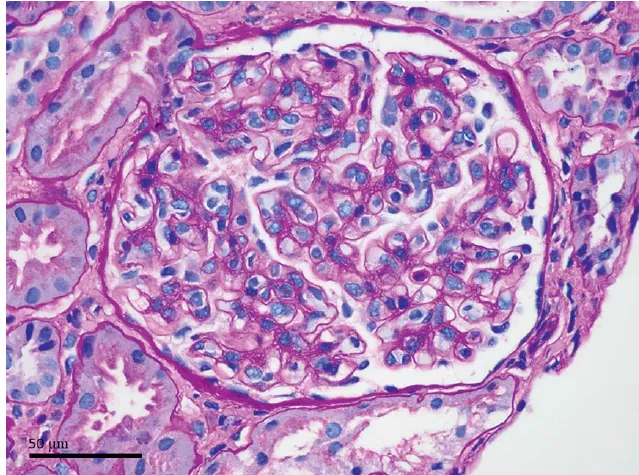

Um homem de 70 anos, com histórico de transplante renal de doador falecido devido a doença renal policística, apresentou-se no departamento de emergência com pneumonia intersticial e hipercalcemia. Ele havia recebido o transplante há um ano antes e interrompeu o uso de valganciclovir e trimetoprima/sulfametoxazol no terceiro mês após o transplante devido à mielotoxicidade associada a esses

medicamentos. Recentemente, o paciente tinha apresentado hipercalcemia progressiva com hipofosfatemia concomitante e níveis elevados de paratormônio (PTH).

A investigação diagnóstica subsequente revelou pneumonia por Pneumocystis jirovecii (PPJ). Apesar do

renal. PJP e citomegalovírus são complicações infecciosas graves, embora sua prevalência tenha sido reduzida com o uso de tratamentos profiláticos como valganciclovir e trimetoprima/sulfametoxazol. A hipercalcemia associada à PPJ está sendo cada vez mais relatada em pacientes transplantados renais, e

acredita-se que a conversão aumentada de vitamina D nativa para ativa por macrófagos ativados em tecido granulomatoso seja o principal mecanismo patogênico. Os achados laboratoriais deste caso - hipercalcemia, altos níveis de vitamina D ativa e baixos níveis de 25-hidroxivitamina D - são consistentes com essa hipótese.